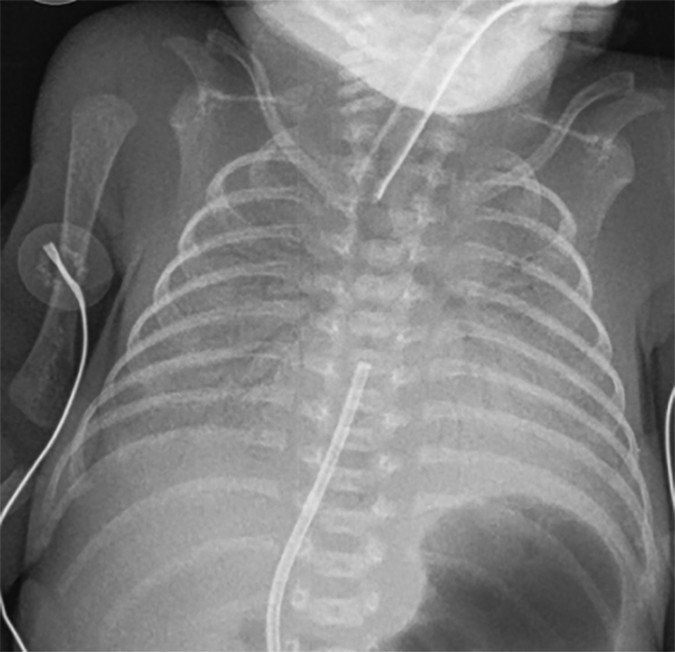

HMD / RDS (Hyaline Membrane Disease / Respiratory Distress Syndrome) Diffuse bilateral granular ("ground-glass") pattern; air bronchograms; low lung volumes Premature infant; surfactant deficiency; improves with surfactant therapy

Neonatal Pneumonia Indistinguishable from HMD on CXR; may show focal consolidation Consider in Group B Strep (GBS) exposure, maternal fever, prolonged rupture of membranes; blood cultures essential

HMD vs. neonatal pneumonia: These two diagnoses are radiographically indistinguishable. In any premature infant with a diffuse granular pattern, especially with risk factors (maternal GBS colonization, prolonged rupture of membranes, maternal fever), treat empirically for pneumonia while awaiting cultures.